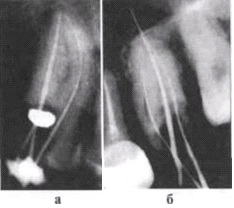

Рис. 6-2. Изгиб инструмента в корневом канале при

недостаточном вскрытии полости зуба. Рентгенограмма